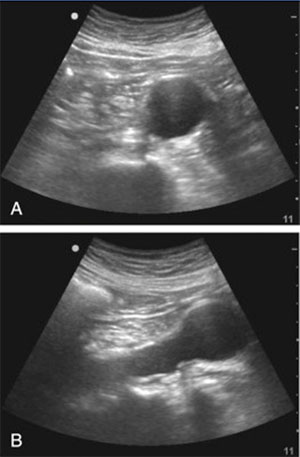

آئورت رو ک پیدا کردی ترنسدوسر رو بیاری پایین تقریبا تا کمی بالای ناف، دو شاخه شدن آئورت به شریان های ایلیاک مشترک رو میبینی

قطر آئورت شکمی باید هم در قسمت پروگزیمال و هم دیستال ارزیابی بشه

مثلا در این کیس آنوریسم در دیستال آئورت شکمی ایجاد شده عکس A نمای عرضی و B نمای طولی آئورت هست :